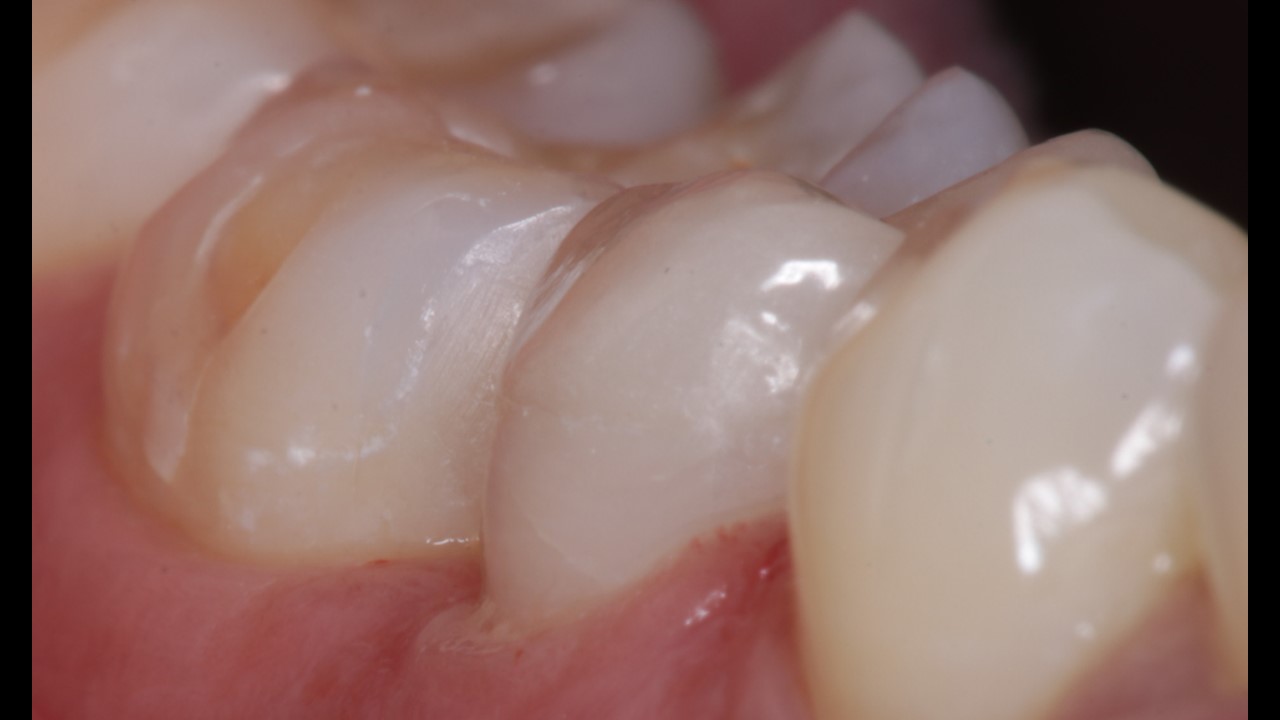

Patient presented with pain and discomfort in the lower right second premolar. Pain was of radiating type accompanied with food lodgement. On examination, the lower right 2nd premoalr was decayed with a portion of the distal surface lost due to the process of deacy. Examination alos revealed decay of the molar on the mesial side. Typical presentation that accompanies food lodgement and decay.

Filling in lower right 1st molar.

Post (fiber) and core , Emax onlay